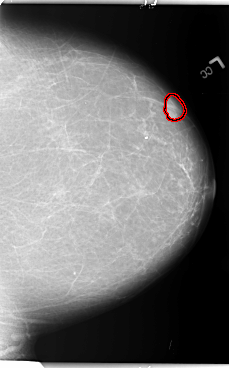

FILE: B_3011_1.LEFT_MLO.OVERLAY

TOTAL_ABNORMALITIES 1

ABNORMALITY 1

LESION_TYPE MASS SHAPE LOBULATED MARGINS CIRCUMSCRIBED

ASSESSMENT 4

SUBTLETY 5

PATHOLOGY BENIGN

TOTAL_OUTLINES 1

BOUNDARY